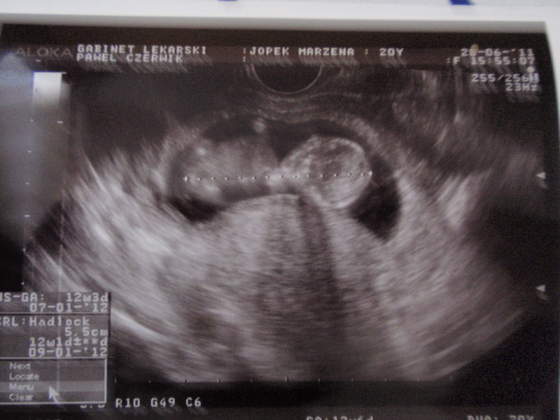

Kochane własnie wróciłam od lekarza:-) z dzidzią wszytko w prządku:happy2:ma 5,5 cm a ma 2 nóżki, rączki, wszystkie paluszki i miewa się bardzo dobrze:-)ja mam tylko anemię... ale najważniejsze dziecko;-)

To moja pociecha :-) P6282310.jpgP6282311.jpg